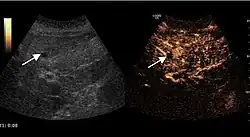

The ultrasound appearance is a well defined lesion, with very thin, almost unapparent walls, without circulatory signal at Doppler or CEUS investigation. The content is transonic suggesting fluid composition. The presence of membranes, abundant sediment or cysts inside is suggestive for parasitic, hydatid nature. Posterior from the lesion the acoustic enhancement phenomenon is seen, which strengthens the suspicion of fluid mass. They typically displace normal liver vessels but no vascular or biliary invasion occurs.

-

Liver cyst -

Hydatid liver cyst. Diagnostic criteria are the presence of membranes and sediment inside.